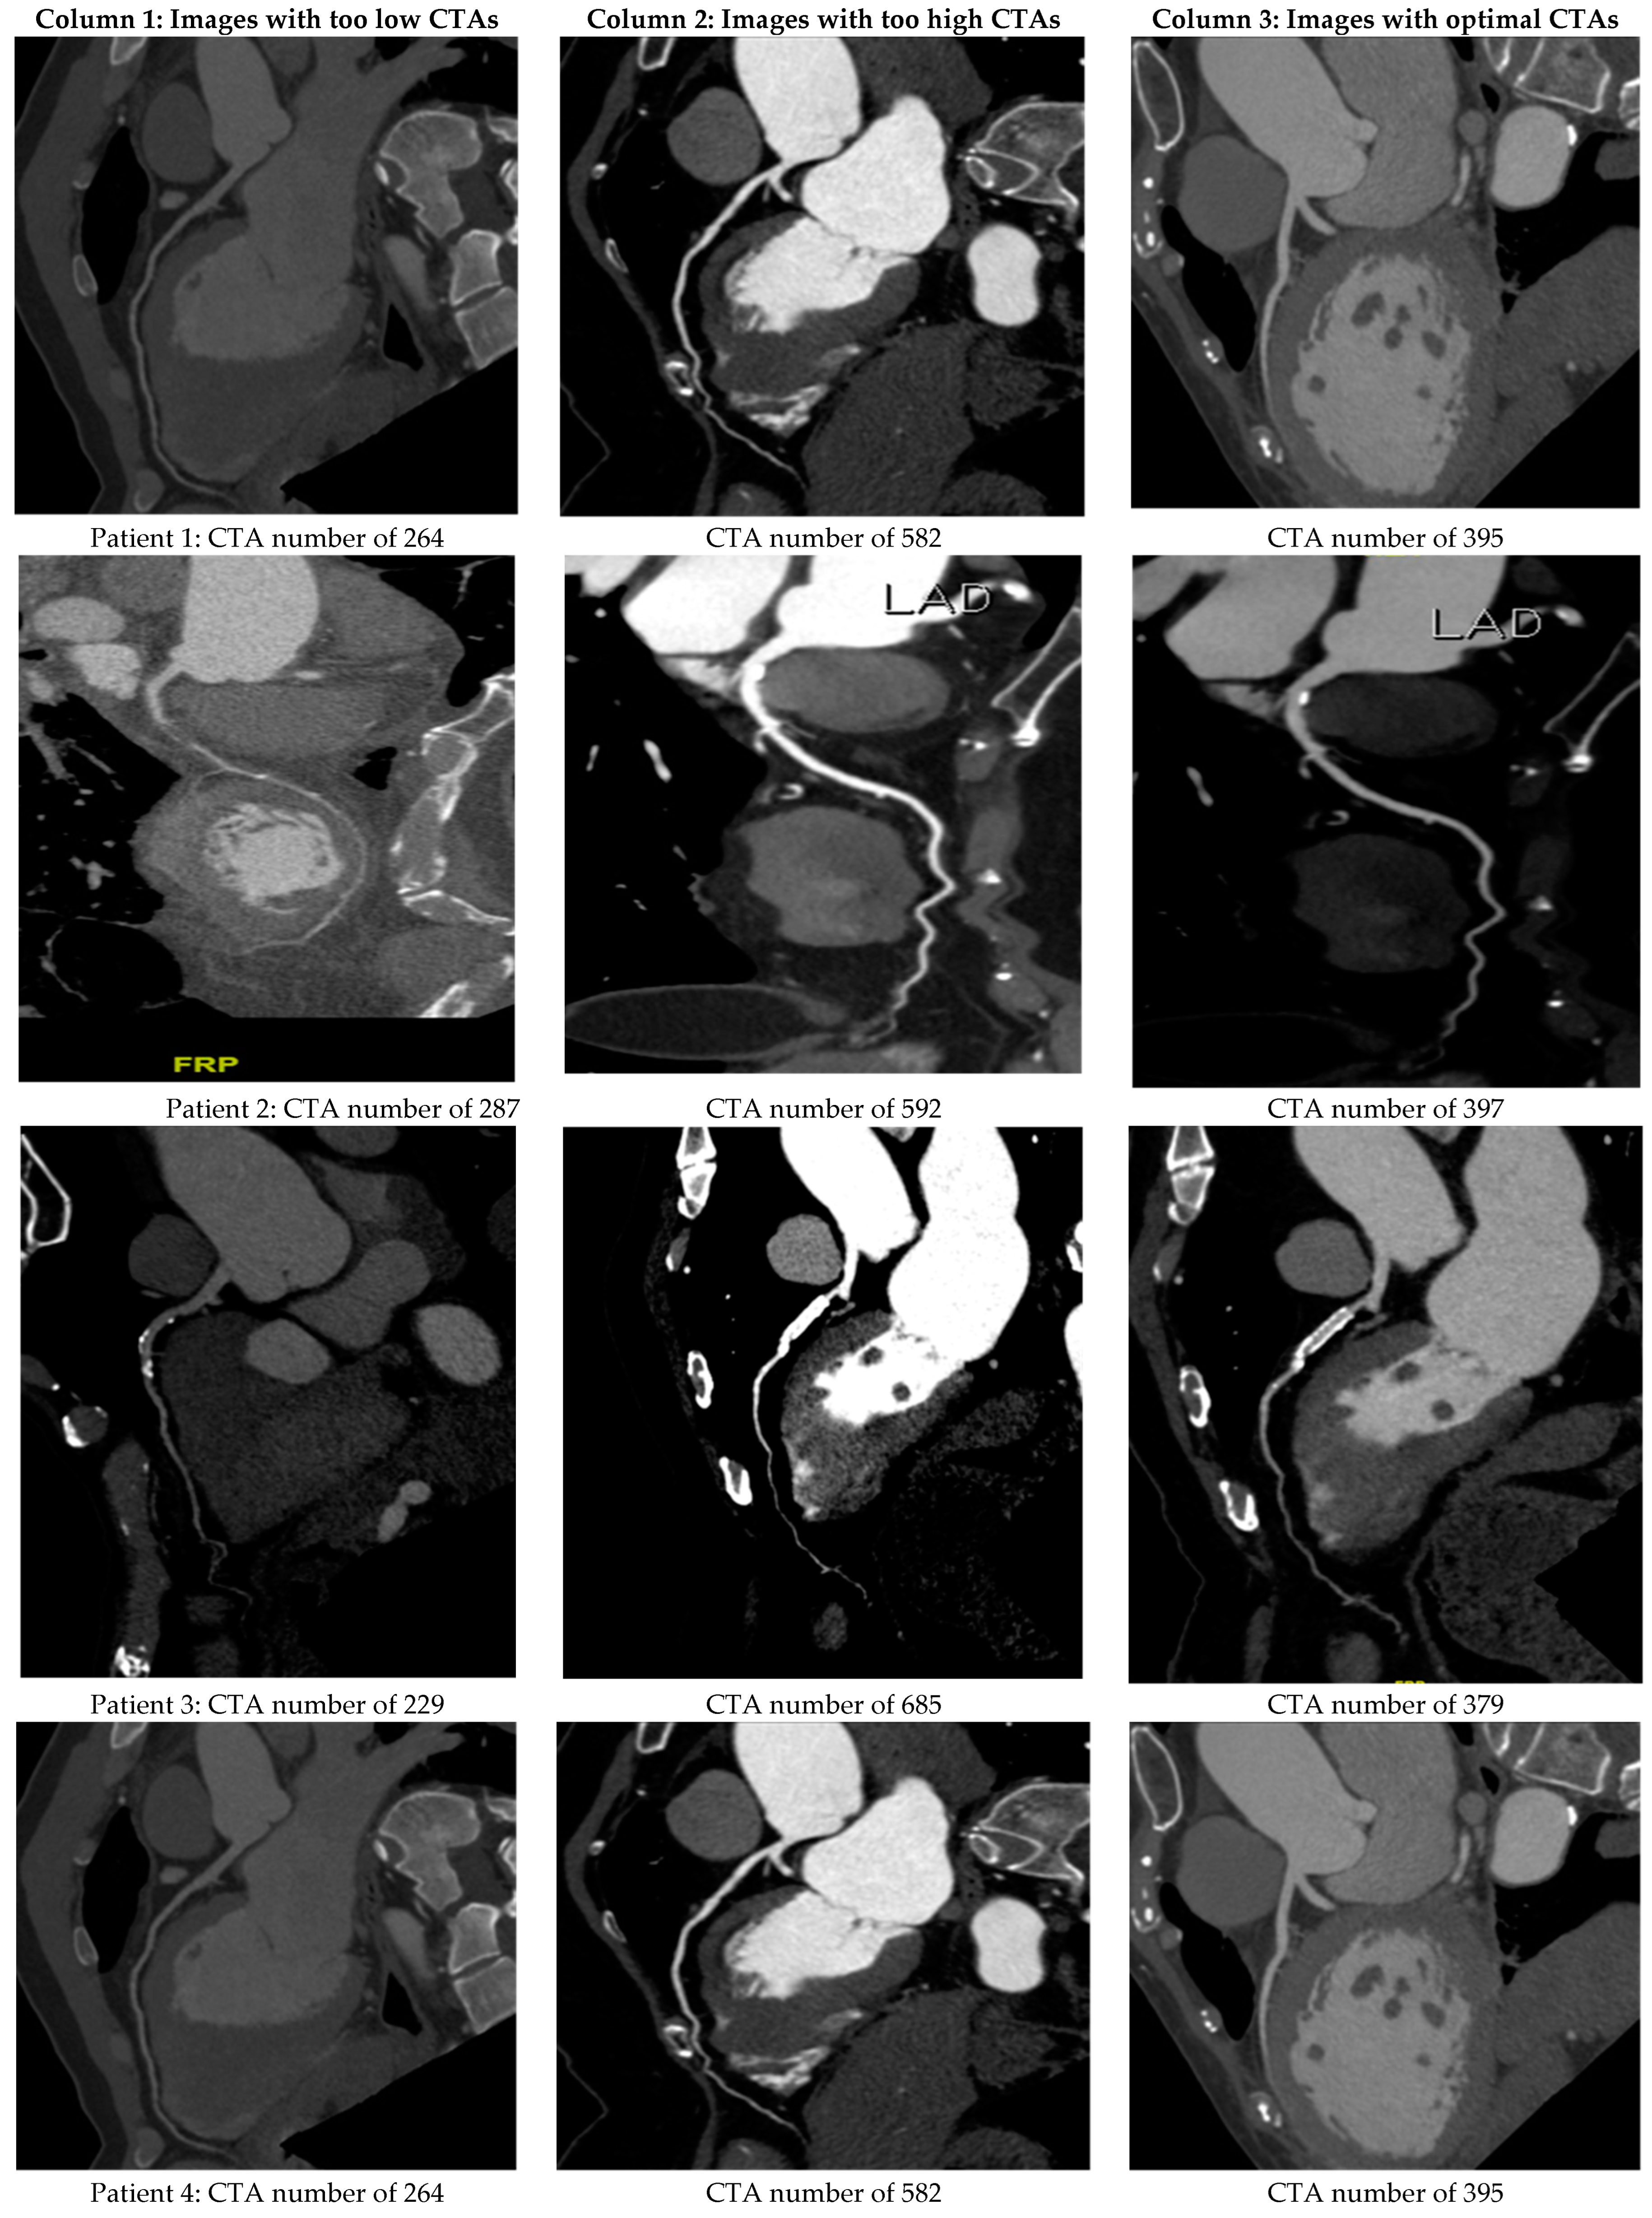

4.1. Verifying the Predicted CTA Number of LA by the Derived Semi-Empirical Formula

4.3. In Vivo Testification of 65 Patients